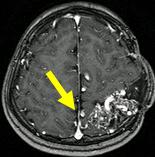

文字方塊: 每年磁共振造影追蹤動靜脈畸形可見逐年消失

2004.07.26

文字方塊: 病患A 14歲 男性

診斷:動靜脈畸形